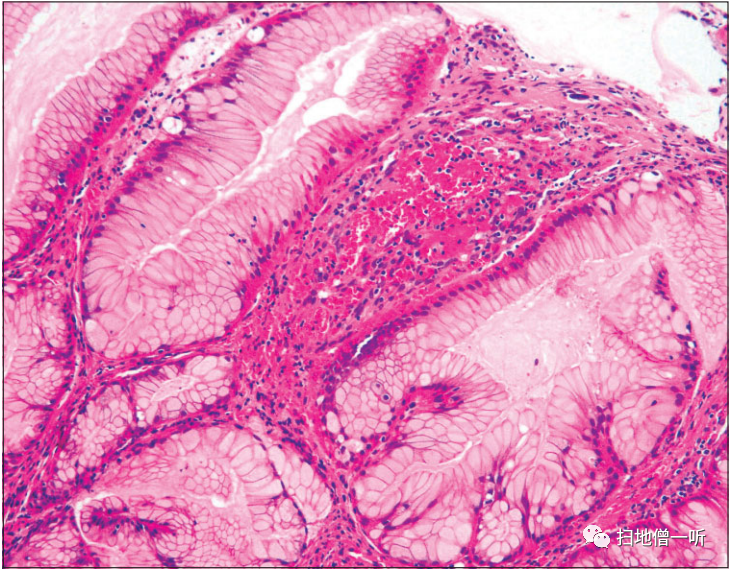

▲在增生性息肉(红色箭头)的活检标本中,息肉表层的小凹上皮是增生性的,但是没有发现异型性。

因使用PPI而发现胃增生性息肉增大的病例。通过投用PPI/P―CAB,贲门部的增生性息肉显著增大,使用Bonoprazan 20mg时,血清胃泌素值为2820 pg/ml,显示出显著的高值。将Bonoprazan变更为雷贝拉唑后,变更后2周内镜检查发现息肉缩小,血清胃泌素值降低到970pg/ml。在病理组织学上,在增生性息肉中发现了小凹上皮的显著增生性变化,但没有异型性。在附近的胃底腺息肉中,在组织学上发现了PCP样所见。